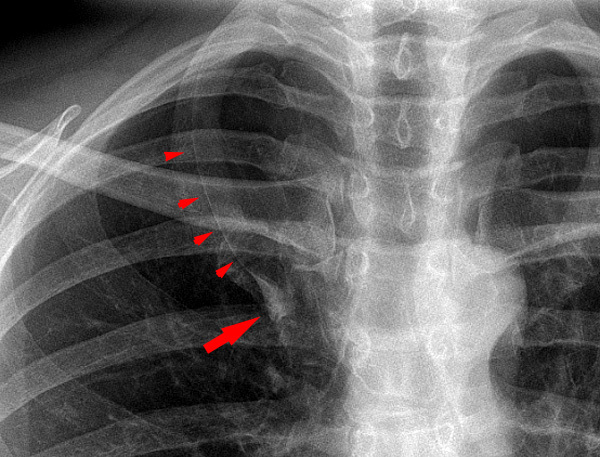

Right Upper Lobe atelectasis

The reverse S sign of Golden is seen in right upper lobe collapse.

The juxtaphrenic peak sign is a peridiaphragmatic triangular opacity caused by diaphragmatic traction from an inferior accessory fissure or an inferior pulmonary ligament.